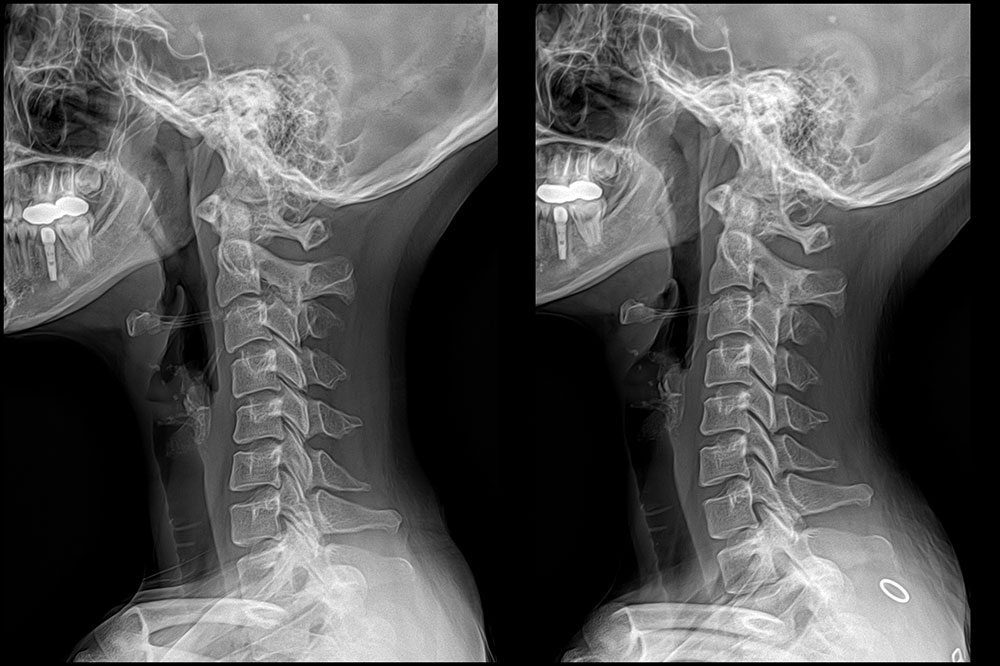

ÃÊÀ½ÆÄÁø´Ü ÇÁ·Ñ·ÎÄ¡·á ü¿ÜÃæ°ÝÆÄ µµ¼öÄ¡·á ¿ÀÇǽºÁúȯ °üÀý¿°Ä¡·á Ä¡·á Àü/ÈÄ »çÁø Ä¡·á Àü/ÈÄ »çÁø °ÅºÏ¸ñ µµ¼öÄ¡·á 10ȸ ÈÄ °ÅºÏ¸ñ µµ¼öÄ¡·á 8ȸ ÈÄ Ç㸮ÅëÁõ¡¤´Ù¸®Àú¸² µµ¼öÄ¡·á 10ȸ ÈÄ °ñ¹Ý Ʋ¾îÁü µµ¼öÄ¡·á 12ȸ ÈÄ Ã´Ãß Ãø¸¸Áõ ¹× Ç㸮ÅëÁõ µµ¼öÄ¡·á 15ȸ ÈÄ